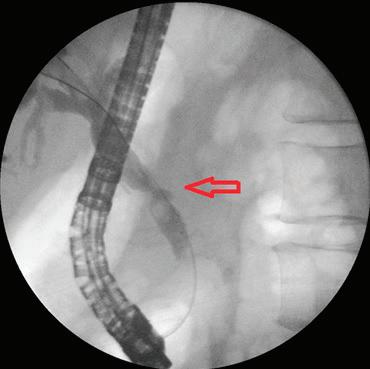

ЛЕЧЕНИЕ СПОРЕД ВИДА НА СТРИКТУРАТА Разработването на златен стандарт за ен доскопска терапия за ДЖС е ограниче но от факта, че няма приета класификация за стриктурите. Докато класификацията на

анастмозата

при пациент със стеноза на хепатико-йе юноанастомозата,

СТРИКТУРИ ТИП 2 Стриктури от тип 2 възникват в прокси малната част на д. хо ледохус или д.хепа тикус комунис, като стриктури на анасто мозата при чернод робна транспланта ция или стриктури след холецистекто мия. Поставяне на на растващ брой пласт масови стентове, сменяни на всеки 3 месеца в продълже ние на една година, е стандартът за ле чение на тези стрик тури. ДЖС след хо лецистектомия обикновено са къси

Освен това те не са добре проуче ни и са недостатъчно представени в мул тицентрични проуч вания. ESGE предлага временно поставя не на MPS за лечение на ДЖС, последица от холецистекто мия; SEMS може да бъде алтернатива за стриктури, лока лизирани >2 cm от чернодробния кон флуенс. Стриктури те след чернодробна трансплантация мо гат да бъдат анасто мотични (ABS) или неаностомотични би лиарни стенози. За анастомотични били арни стриктури MPS е златен стандарт (Фиг. 6).

щия чернодробен ка нал или в конфлу ГАСТРОЕНТЕРОЛОГИЯ Фиг. 6 Мултистентинг терапия при пациент със стеноза на

след чер нодробна трансплатация Фиг. 7 ЕРХПГ

поставени два пластма сови стента

СТРИКТУРИ ТИП 4 Тип 4 са хирургични анастомози, като хепатико-йеюноанастомоза, които могат да бъдат предизвика телство за терапия поради промене на анатомия. Традиционно подходът е перкутанен трансхепатален билиа рен дренаж (PTBD), но ако центърът има опит и наличност, ERCP също е привлекателна и най-минимално инвазивна опция. При тези пациенти може да бъде обсъден ехо-ендос копски навигиран билиарен дре наж[24] (Фиг. 7).